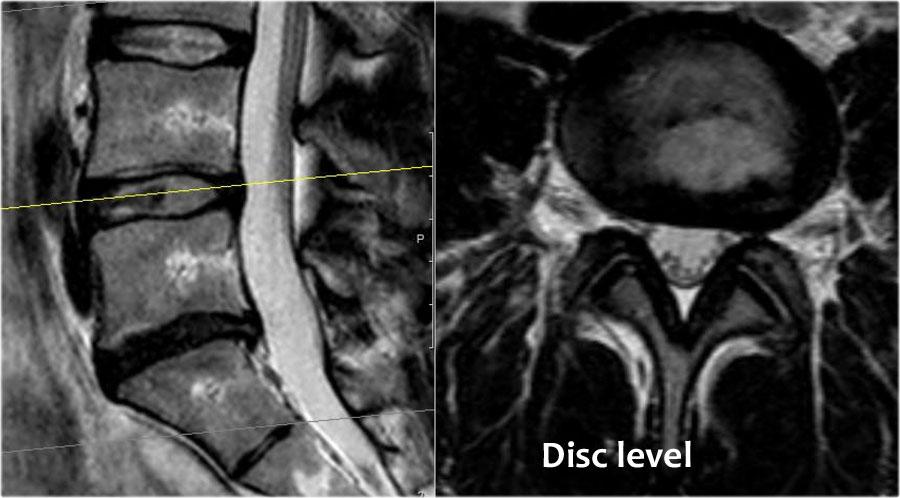

Ở bệnh nhân có triệu chứng chèn ép rễ thần kinh, có bốn mức độ cần được khảo sát:

- Mức độ đĩa đệm.

Đây là vị trí phổ biến nhất gây chèn ép thần kinh.

Chủ yếu do thoát vị đĩa đệm và ít thường gặp hơn do hẹp ống sống. - Mức độ ngách bên.

Cuộn qua các hình ảnh để quan sát đường đi của các rễ thần kinh tại mức độ đĩa đệm, ngách bên, lỗ liên hợp và ngoài lỗ liên hợp.

Tại mỗi mức độ có thể thấy các bệnh lý đặc trưng, nhưng có sự chồng lấp đáng kể.